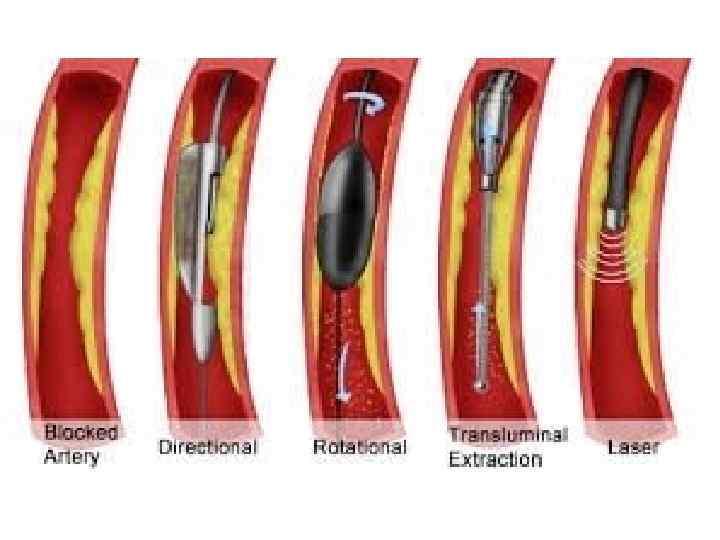

Тікелей атероэктомия Ротационды атероэктомия • Әктенбеген бляшка кезінде қолд • Аорт төм бөл. ж/е бифуркацияда • Әктенген, ұз 20 мм бляшка кез-де • Алмазды наконечнигі бар бур ар-ы бляшканы құмға айн-ы

Тікелей атероэктомия Ротационды атероэктомия • Әктенбеген бляшка кезінде қолд • Аорт төм бөл. ж/е бифуркацияда • Әктенген, ұз 20 мм бляшка кез-де • Алмазды наконечнигі бар бур ар-ы бляшканы құмға айн-ы